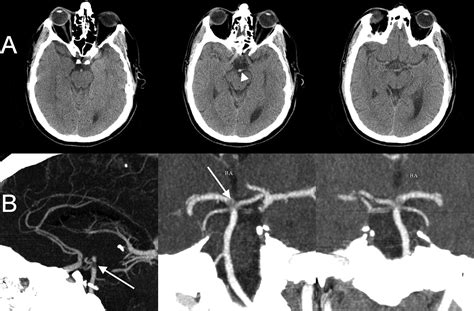

Diagnosis and Emergency Imaging

When a patient arrives at the emergency department with suspected neurological deficits, medical professionals follow a strict protocol. Speed is the priority. Doctors will typically perform a neurological exam and immediately order imaging studies to differentiate between an ischemic stroke and a hemorrhagic stroke.

Standard diagnostic tools include:

• Computed Tomography (CT) Scan: Often the first test, used primarily to rule out bleeding.

• CT Angiography (CTA): Provides a detailed view of the blood vessels to identify the exact location of a blockage.

• Magnetic Resonance Imaging (MRI): More sensitive than a CT scan for detecting early signs of ischemia in the brainstem.

• Magnetic Resonance Angiography (MRA): Similar to CTA, it maps the blood vessels without the need for iodinated contrast in some cases.